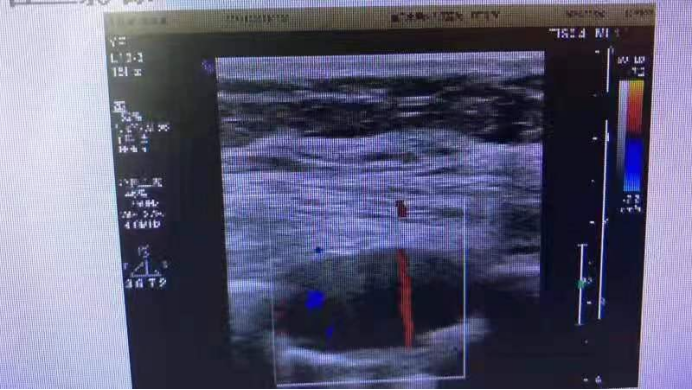

二、彩超显示图片

超声引导下经皮肺穿刺活检术是通过超声引导把一根活检针刺入病灶组织中,然后进行采集,获取病灶的组织标本,为病理活检的一种主要方法。